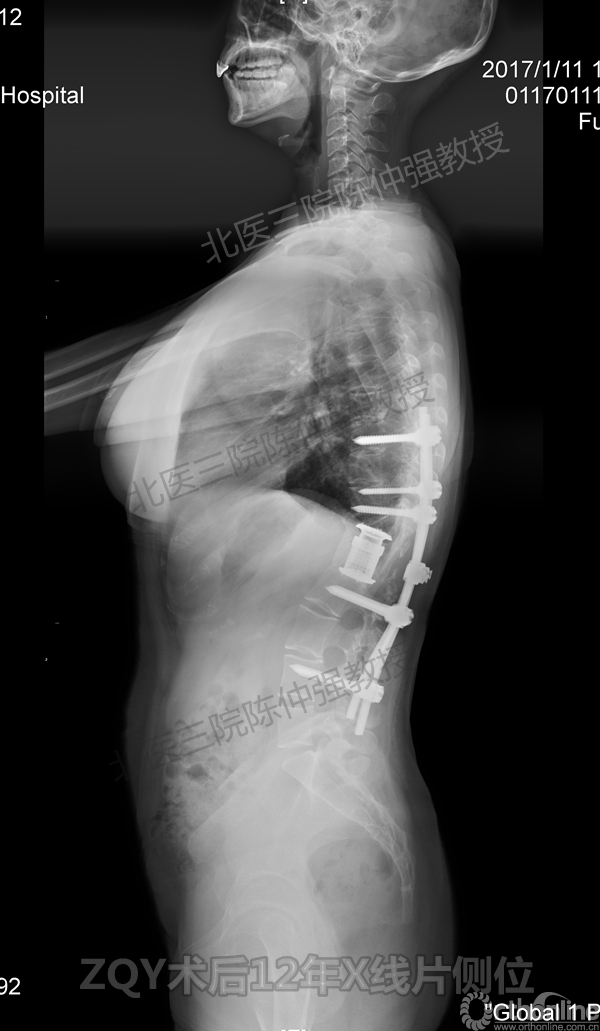

2005年,陈仲强教授在AOSpine年会上分享了一例胸腰椎陈旧结核性侧后凸畸形病例。资料如下:

ZQY术前

ZQY术后

ZQY术后半年

ZQY术后1年

ZQY术后2年

ZQY术后5年

ZQY术后12年

患者女性17岁,胸腰椎陈旧结核性侧后凸畸形,局部呈“麻花状”扭转,无神经功能受损表现。2005年,陈仲强教授带领团队实施后路+侧前方联合入路脊柱节段切除、双轴旋转矫形术。术后患者外观显著改善,神经功能正常。术后随访证实患者截骨矫形节段骨性融合良好,矫形效果持续良好。